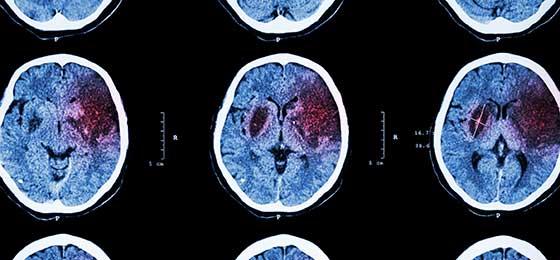

Following the JPND call "Harmonisation and Alignment in Brain Imaging Methods for Neurodegeneration", ten projects were selected for funding. Swiss researchers are participating in one project.

In total, 18 consortium proposals were submitted in response to the EU JPND rapid-action call 2016. At the end of a highly competitive selection process, ten projects were selected for funding. Swiss researchers are participating in the project "Harmonisation of acquisition and processing of brain imaging biomarkers for neurodegenerative diseases: a strategic research agenda for best practice guidelines".

The project involves 25 researchers from 11 European countries (Belgium, France, Germany, Italy, Slovenia, Sweden, the Czech Republic, the Netherlands, Turkey, United Kingdom and Switzerland), and is coordinated by the Swiss scientist Giovanni Frisoni (Geneva). The objective of this working group is to address issues of key relevance for the future use of brain imaging techniques in the above-mentioned fields of research. The project will be financially supported by the SNSF in the coming year.